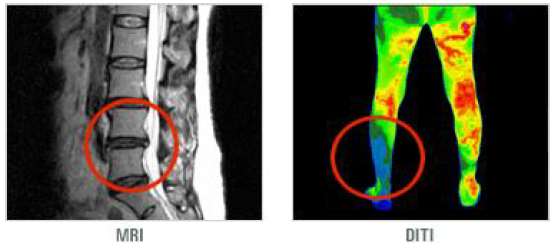

(4)MRI : 가장 정확한 진단 방법으로 최근 초기검사로 많이 이용한다. 특히 척수신경의 이상유무를 가장 잘 보여주는 검사로서 협착증의 정도를 요추부 전체 영상으로 볼 수 있어 수술 계획의 수립에 필수적이다.

(6)적외선 체열 진단검사(DITI) :인체에서 자연적으로 방출되는 극미량의 적외선을 감지하여 인체의 통증부위 및 질병부위의 미세한 체열변화를 컬러영상으로 나타내줌으로써, 인체의 이상유무와 질병여부를 판단한다.